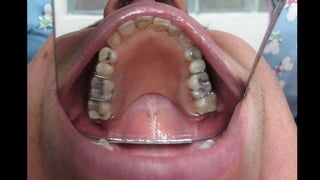

El documento trata sobre la cirugía bucal para plastía del proceso alveolar utilizando hueso humano y factores de crecimiento. También menciona los cuidados postoperatorios, que incluyen el uso de hielo, reposo, dieta líquida y antibióticos, evitando antiinflamatorios no esteroides. Se proporciona información adicional sobre las páginas web relacionadas con cirugía maxilofacial.